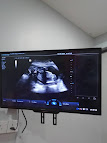

Alhamdulillah dah hampir 6 bulan pregnant..